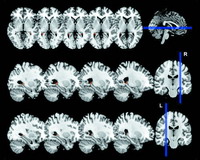

出租车司机大脑具有较大海马区

出租车司机的大脑与众不同。

研究人员在10多年前便已知道,那些出租车司机中的精英们——他们经过长期的训练而掌握了一门绝技:由25000条街道构成的心理地图——拥有一个大于平均值的后海马,这一大脑区域与认知及导航有关。

因此一个研究小组在4年的时间里,对3个受试组进行了跟踪调查——一组是成功获得了“绝技”并成为出租车司机的学员,一组是不具备从业资格的学员,最后的对照组则是非出租车司机。

研究人员对受试者进行了测试,并在训练之前、过程中以及结束后对他们的大脑进行了扫描。

研究人员发现,在开始训练之前,具有从业资格的学员的大脑与那些没有从业资格的学员、或非出租车司机的大脑并没有差别。

然而随着出租车司机掌握了更多的信息,他们的海马区也在不断增大,并逐渐改变了他们的大脑。

英国伦敦大学学院的神经学家Katherine Woollett和Eleanor A. Maguire在12月8日的《现代生物学》杂志网络版上报告了这一研究成果。

而不成功的学员的大脑海马区从始至终都是相同的大小,这可能意味着,成功的出租车司机真的拥有一种与生俱来的优势——他们的大脑比别人具有更大的可塑性。